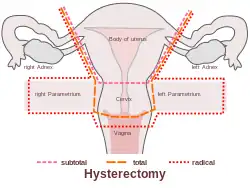

Types

Hysterectomy, in the literal sense of the word, means merely the removal of the uterus. However, other organs such as the ovaries, fallopian tubes, and the cervix are very frequently removed as part of the surgery.[60]

- Radical hysterectomy: complete removal of the uterus, cervix, upper vagina, and parametrium. Indicated for cancer. Lymph nodes, ovaries, and fallopian tubes are also usually removed in this situation, such as in Wertheim's hysterectomy.[61]

- Total hysterectomy: complete removal of the uterus and cervix, with or without oophorectomy.

- Subtotal hysterectomy: removal of the uterus, leaving the cervix in situ.

Subtotal (supracervical) hysterectomy was originally proposed with the expectation that it may improve sexual functioning after hysterectomy, it has been postulated that removing the cervix causes excessive neurologic and anatomic disruption, thus leading to vaginal shortening, vaginal vault prolapse, and vaginal cuff granulations.[62] These theoretical advantages were not confirmed in practice, but other advantages over total hysterectomy emerged. The principal disadvantage is that the risk of cervical cancer is not eliminated, and women may continue cyclical bleeding (although substantially less than before the surgery). These issues were addressed in a systematic review of total versus supracervical hysterectomy for benign gynecological conditions, which reported the following findings:[63]

Supracervical hysterectomy does not eliminate the possibility of having cervical cancer since the cervix itself is left intact and may be contraindicated in women with increased risk of this cancer; regular pap smears to check for cervical dysplasia or cancer are still needed.[66][67]